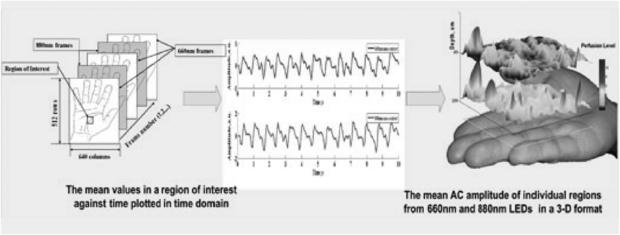

Photoplethysmography imaging (iPPG) is a non-contact imaging method for mapping cardiac synchronous pulsations i.e. perfusion across an area of tissue. iPPG has various forms and can be single wavelength field illumination (near infrared) or dual wavelength illumination (both red and near infrared). iPPG can also be used to determine oxygen saturation by employing algorithms and empirical formulae similar to that of traditional single site contact pulse oximetry. iPPG mapping of pulsatility represents the regional perfusion for the superficial blood vessels including the microcirculation. iPPG has capability for high resolution, fast scanning speeds and can ultimately be of low-cost. The technique can be unreliable where there is significant movement artefact, and correction algorithms are a key part of ongoing technology development. Currently, the literature on iPPG relates to technical advances rather than clinical utility and validity. One very important area with significant commercial potential is its translation to the very low-cost webcam platform. Examples of cardiac synchronous waveforms that can be obtained from the forehead site with iPPG are shown in figure 16.

Standard image High-resolution imageEarly iPPG imaging systems were limited by low frame sampling rates, restricting their clinical use, for example in the assessment of pulse rate and its variability. Developments have been promising in terms of speed and sensitivity. The key physiological parameters i.e. respiration rate, heart and also pulse rate variability (PRV) derived from the iPPG datasets can yield statistically comparable results to those acquired using a contact PPG sensor (Sun et al 2013). Advanced physiological monitoring has been reported by Hu et al (2009, 2010) using opto-physiological modelling to extract information on superficial and deeper tissue blood volume perfusion levels (figure 18).

Figure 18. Cardiac synchronous pulses from a dual wavelength iPPG system for a region of interest on the hand. The 2D pulsatility can be seen. Image processing at two wavelengths with opto-physiological modelling enables a 3D representation for two tissue depths; superficial and deep. (Courtesy of Professor S Hu, Loughborough University.)